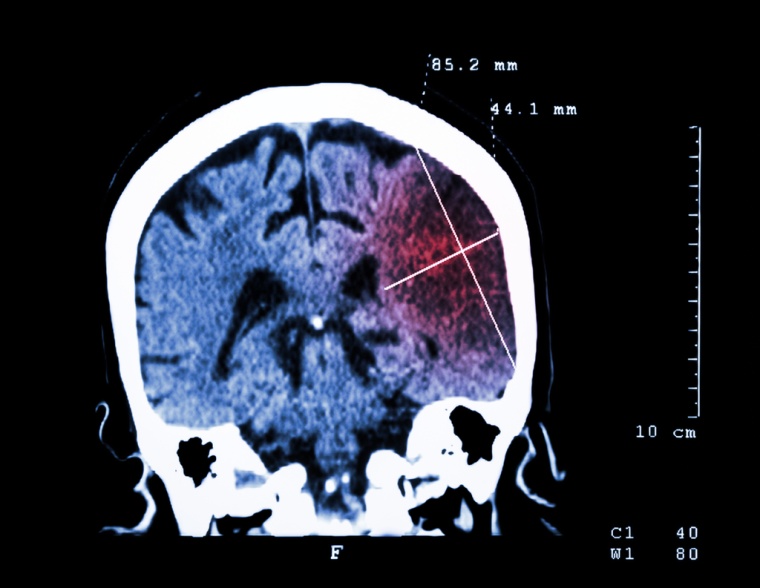

Nach einem Schlaganfall ist schnelles Handeln gefordert. Je früher die Behandlung einsetzt, desto geringer sind in der Regel die Folgeschäden bei den Betroffenen. Doch Geschwindigkeit ist nicht alles: Krankenhäuser sollten darüber hinaus eine ganze Reihe spezieller Qualitätskriterien bei der Behandlung von Patientinnen und Patienten mit einem akuten Schlaganfall erfüllen. Denn je mehr dieser Kriterien sie einhalten, desto weniger der Betroffenen sterben innerhalb der ersten sieben Tage nach ihrer Einlieferung.